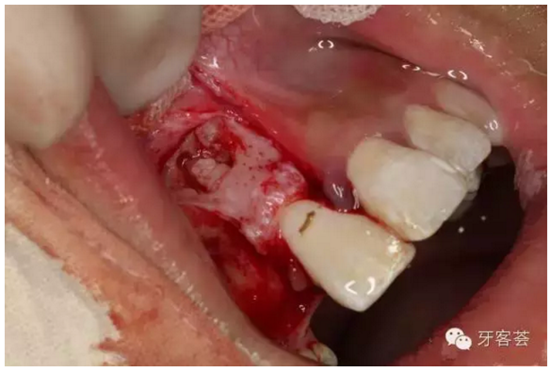

圖6:切開(kāi)、翻瓣、暴露13牙冠。

圖9:清理12牙槽窩

圖10:清理完成的12牙槽窩,并翻瓣暴露11的根尖區(qū)骨壁,骨壁完整、無(wú)破壞。